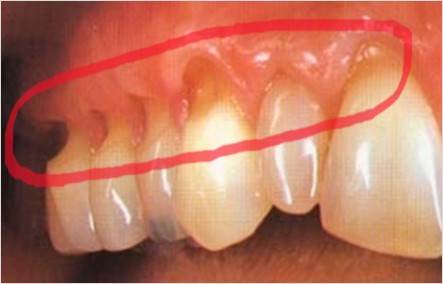

치경부 마모증은 치아의 목 부분, 즉 치경부에 해당하는 치아와 잇몸이 만나는 경계 부위가 V자 모양으로 패이면서 발생하는 현상입니다. 이로 인해 치아가 시리고, 차가운 음식이나 음료를 섭취할 때 통증을 느낄 수 있습니다. 마모된 부위가 점점 더 커지게 되면 충치나 치아 파절 등 다양한 문제로 이어질 수 있어 조기 치료가 중요합니다.

질긴 음식이나 단단한 음식을 자주 씹는 것도 치경부 마모증의 원인 중 하나입니다. 오징어, 육포와 같은 음식은 씹는 과정에서 치아에 큰 부담을 주게 되는데, 특히 이갈이나 이를 꽉 무는 습관이 있다면 치아의 목 부분으로 과도한 힘이 전달되어 마모가 진행될 가능성이 큽니다. 이로 인해 치아 목 부분이 부분적으로 떨어져 나가게 되고, 시간이 지남에 따라 V자 형태의 홈이 점점 깊어지게 됩니다.